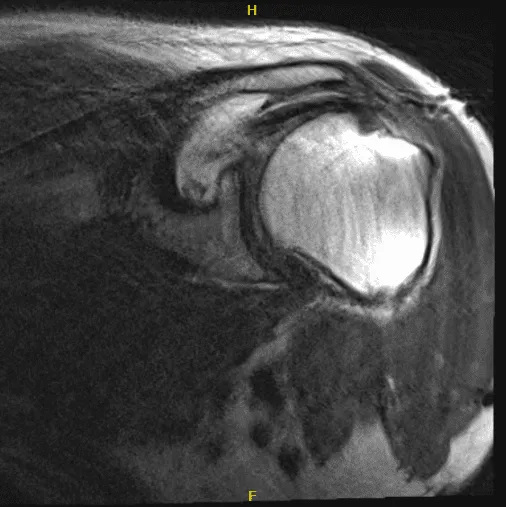

He presented his MRI to me, and we reviewed it. Impression as follows: Status post rotator cuff repair with marked metal artifact slightly limited examination. Suggestion of at least partial tearing of the supraspinatus tendon.

Consider CT arthrogram or ultrasound for further evaluation. High-grade partial tearing of the infraspinatus tendon with possible full-thickness component. Suggestion of biceps tenodesis.

MRI of the left shoulder